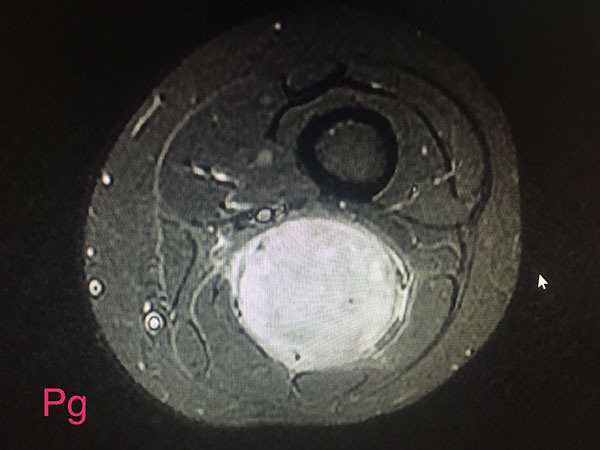

15yrs old girl with large sciatic nerve tumor wondering since 1yr in Jaipur, open biopsy was done elsewhere diagnosed as neurofibromas and she land up with infected bad biopsy scar with discharging sinus

I operated her 5days back with complete removal of tumor along with biopsy scar and track with dissecting nerve fibers from mass and now she has no neurological deficits and full range of movements of knee and foot